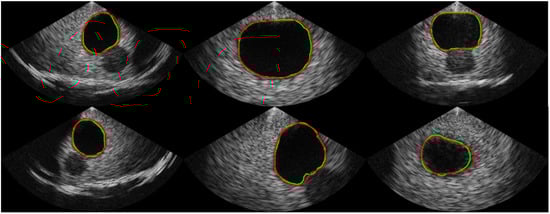

To collect a dataset with high variability, various gain and depth settings were used. The ultrasound bladder images were obtained from two tissue-mimicking phantoms: an intravesical urine volume measurement phantom (US-16, Kyoto Kagaku, Kyoto, Japan) with urine volumes of 50 mL, 150 mL, and 300 mL, and a multimodality pelvic phantom (Model 048A, CIRS, Norfolk, VA, USA). A total of 1306 images with a bladder and 2095 images without a bladder were collected. The bladder images were randomly divided into 1044 images for training and 262 images for validation, with each image labeled with a corresponding mask for the segmentation task. The images without a bladder were divided into 1675 images for training and 420 images for validation for the classification task. To capture ROIs of various sizes, the dataset was collected by randomly selecting locations with a free hand on a static phantom. To validate the size and distribution of the dataset, the accuracies on the training phase and validation phase are compared. Examples of the dataset are shown in Figure 2.

Figure 2.

Examples of the acquired dataset. The first and second rows show images with a bladder, and the green line indicates the boundary of the mask label from human labelers. The third row represents images without a bladder, indicating that the bladder was not observed.